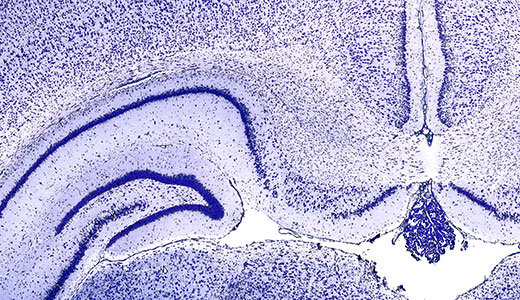

Die Schüler*innen erfahren, wie Nervengewebe sichtbar gemacht und dadurch unterschiedliche Strukturen differenziert werden können. Auf diese Weise wird die Organisation unterschiedlicher Gewebestrukturen vermittelt und ein Einblick in die Vielfalt von histologischen Methoden geboten.

Cortex - Zellen und Schichten

Die Schüler:innen erarbeiten anhand der Nissl-Färbung die Organisation des Cortex. Dafür betrachten sie unterschiedliche Zelltypen und quantifizieren deren Packungsdichte in verschiedenen Bereichen. Weiterhin setzen sich die Schüler:innen mit der charakteristischen Schichtung im Nervengewebe auseinander.